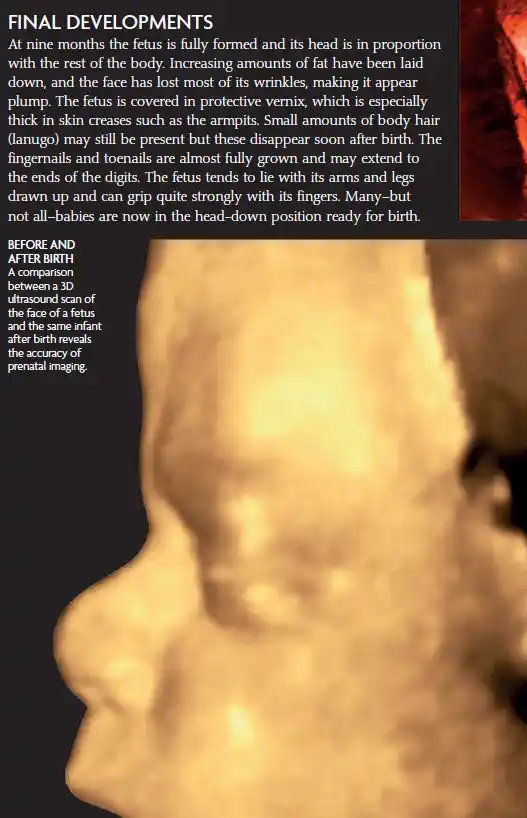

A comparison image showing a 3D ultrasound scan of a fetus’s face before birth and a photo of the same infant after birth, along with an infographic explaining the final developmental stages of the fetus at 9 months.

At 41 weeks pregnant, your baby is fully developed and just about ready to meet the world. Here’s a breakdown of your baby’s development: